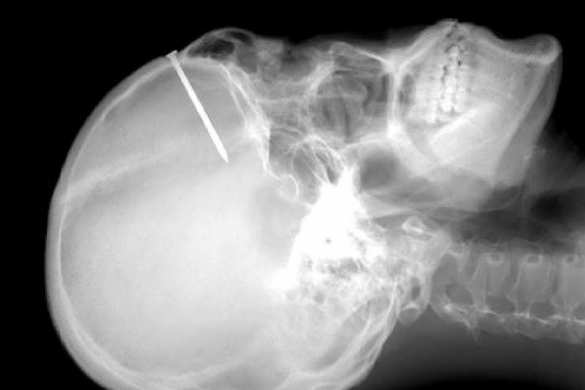

Этот препарат представляет собой сложную питательно-строительную смесь, усиленную активаторами регенерации. Такой подход позволяет организму запустить собственный механизм восстановления костной ткани. Материал может использоваться при оперативных вмешательствах на костных тканях челюстно-лицевой области, для заполнения дефектов костной и хрящевой тканей в стоматологии и хирургии»